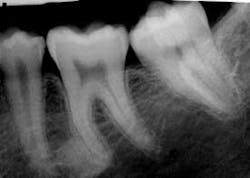

As you take his radiographs, you also make a PA of the tooth (see Figure 2). You confer with the dentist, to determine her opinion concerning the etiology of the odd molar. As you both view the clinical slide and radiograph, the diagnosis is unclear. You are confused about whether a separate root system is present.

Figure 1: Clinical slide of tooth #18 with additional adjoining tooth in question. Photo courtesy of Kathryn Jendrasik-Savitsky, DDS. Figure 2: The radiograph vaguely supports two separate root canal systems. Also noted in the radiograph is a small focus of dense, radiopaque bone between the bicuspid and the first molar. This was diagnosed as “as a small zone of idiopathic osteosclerosis.” Photo courtesy of Jessica Huffman, RDH. Figures 3, 4: Gemination. Photos courtesy of Lippincott Williams & Wilkins from “General and Oral Pathology for the Dental Hygienist.” and Dr. Harvey Kessler. Figure 5: Fusion. Photo courtesy of Lippincott Williams & Wilkins from “General and Oral Pathology for the Dental Hygienist” and Dr. Harvey Kessler.

Significant radiographic features: Radiographic diagnosis is the key factor in distinguishing gemination and fusion, and a variety of appearances may be noted in both gemination as well as fusion. With gemination, the root canal system will appear normal, but will split as it moves toward the crown.

The pulp chambers may appear noticeably large. In this case, the pulp chamber does appear somewhat separate (see Figure 2). Also noted in the radiograph is a small focus of dense, radiopaque bone between the bicuspid and the first molar. This was diagnosed “as a small zone of idiopathic osteosclerosis.”

Technically, the definition of gemination requires the tooth count to be normal when the tooth in question is counted as one tooth. In this case, since the third molar is not present, the definition for gemination is fulfilled as well. However, also with the definition of gemination, the teeth would share the same root canal system. In this case, that aspect is in question since the radiograph vaguely supports two separate root canal systems.